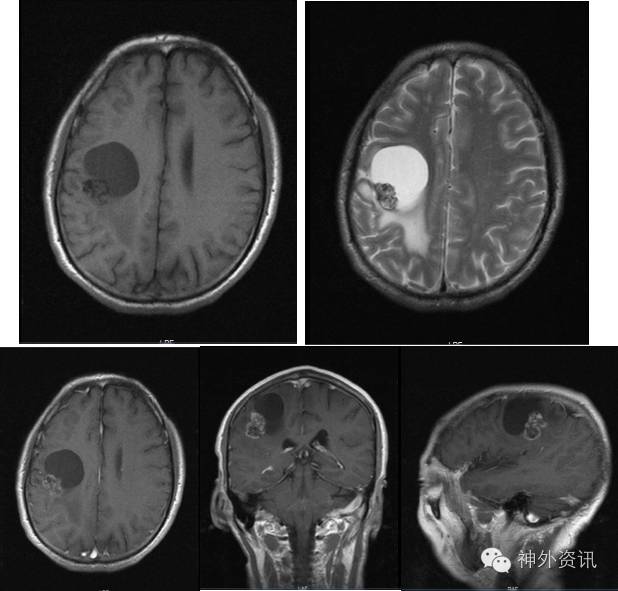

患者1年前无明显诱因下出现左侧手指麻木,中指和无名指为甚,当时无活动障碍,未予重视。后手指麻木症状逐渐加重,伴远端关节活动不利,遂于当地医院就诊,查头颅增强MRI示:右侧额顶部占位,星形胶质细胞瘤首先考虑(图1)。为求进一步治疗转来我院。

图1. 右侧额顶叶内见不规则囊实性占位,前内方为囊样信号影,边界清楚无强化,后外方可见一不均匀结节,T2WI混杂低信号,不均匀强化,周围可见水肿带。脑室、脑池和脑沟形态及位置无殊。中线结构未见移位。